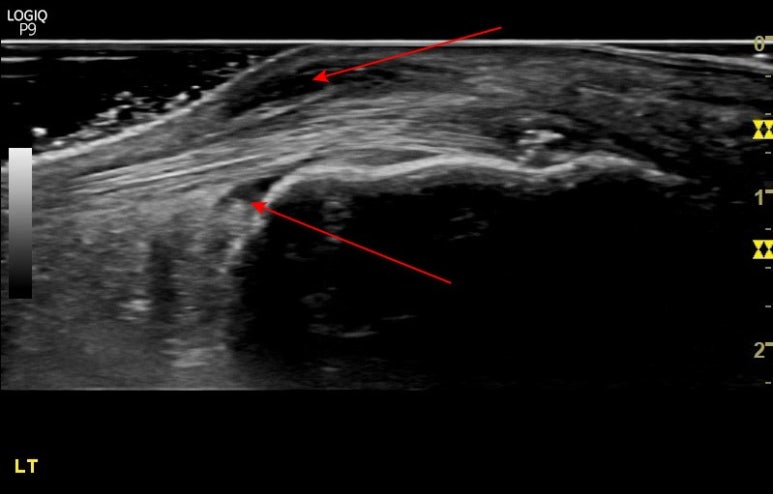

아킬레스건 부음, 골극

뒷꿈치가 툭 튀어나오면서

아킬레스건이 부었다는 말씀을

많이 하시는데요.

가장 흔한 것은

뼈가 자라나는 것입니다.

힘줄이 긴장되면서

뼈를 계속 잡아당기면

뼈 세포가 옮겨가며

뼈가 자라나게 됩니다.

이걸 spur(스퍼),

우리 말로 골극

이라고 합니다.

세번째 환자분은

경기도 파주에서 오신 분인데요.

맨눈으로 봐도

뒤꿈치가 부어보였는데

손으로 만져보니

엄청 딱딱하고요.

초음파 영상으로 봐도

뼈가 자라난 경우였어요.

저런 골극은

굳이 깎아내지 않고도

아킬레스건 통증이

확 좋아질 수 있습니다.